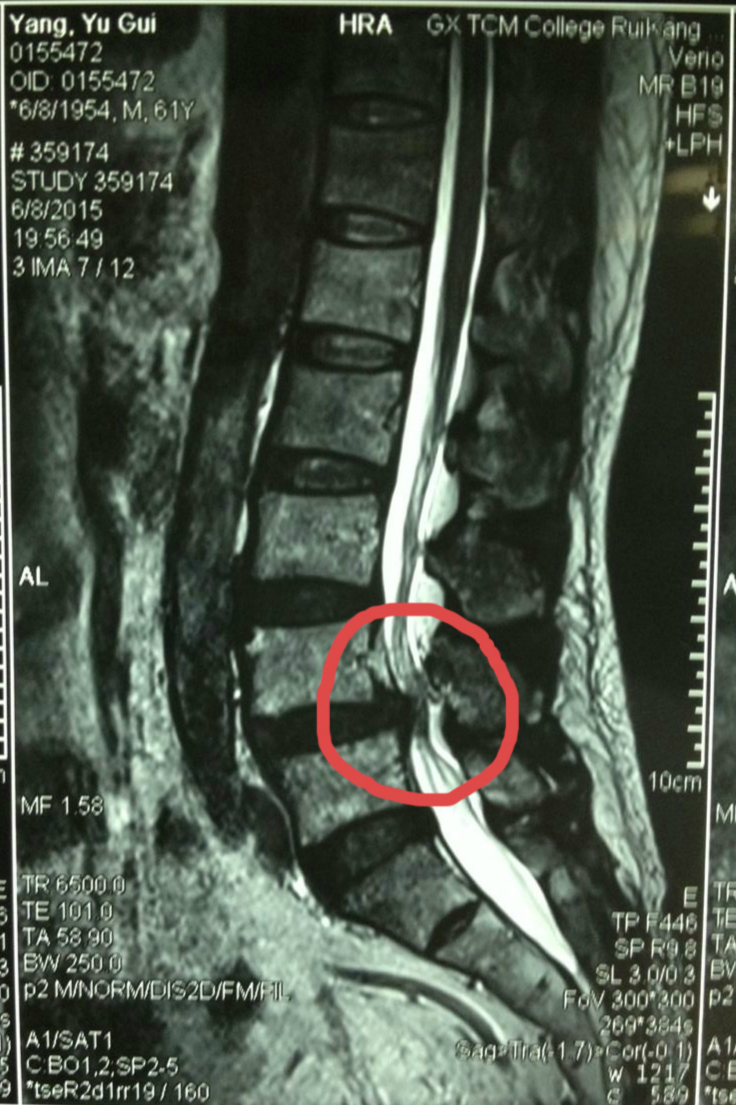

三年寻医无果 微创轻松去腰突

杨老师退休后从贵港来到南宁帮儿子带孩子,一家人其乐融融,可是三年前杨老师的惬意日子出现了小烦恼,抱孙子的时候突然腰疼,然后两条腿也有...

发布时间:2015-06-29 来源: